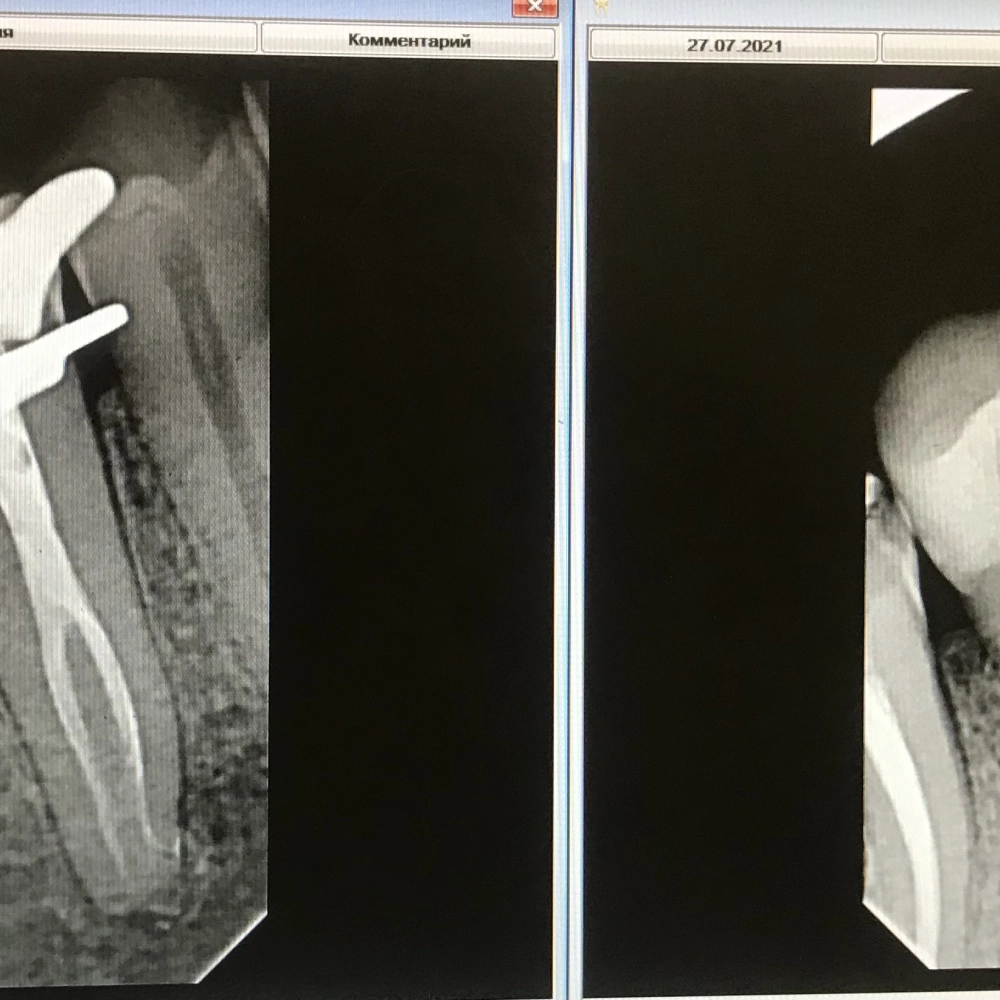

перелечивание зуба

До

После

перелечивание зубов